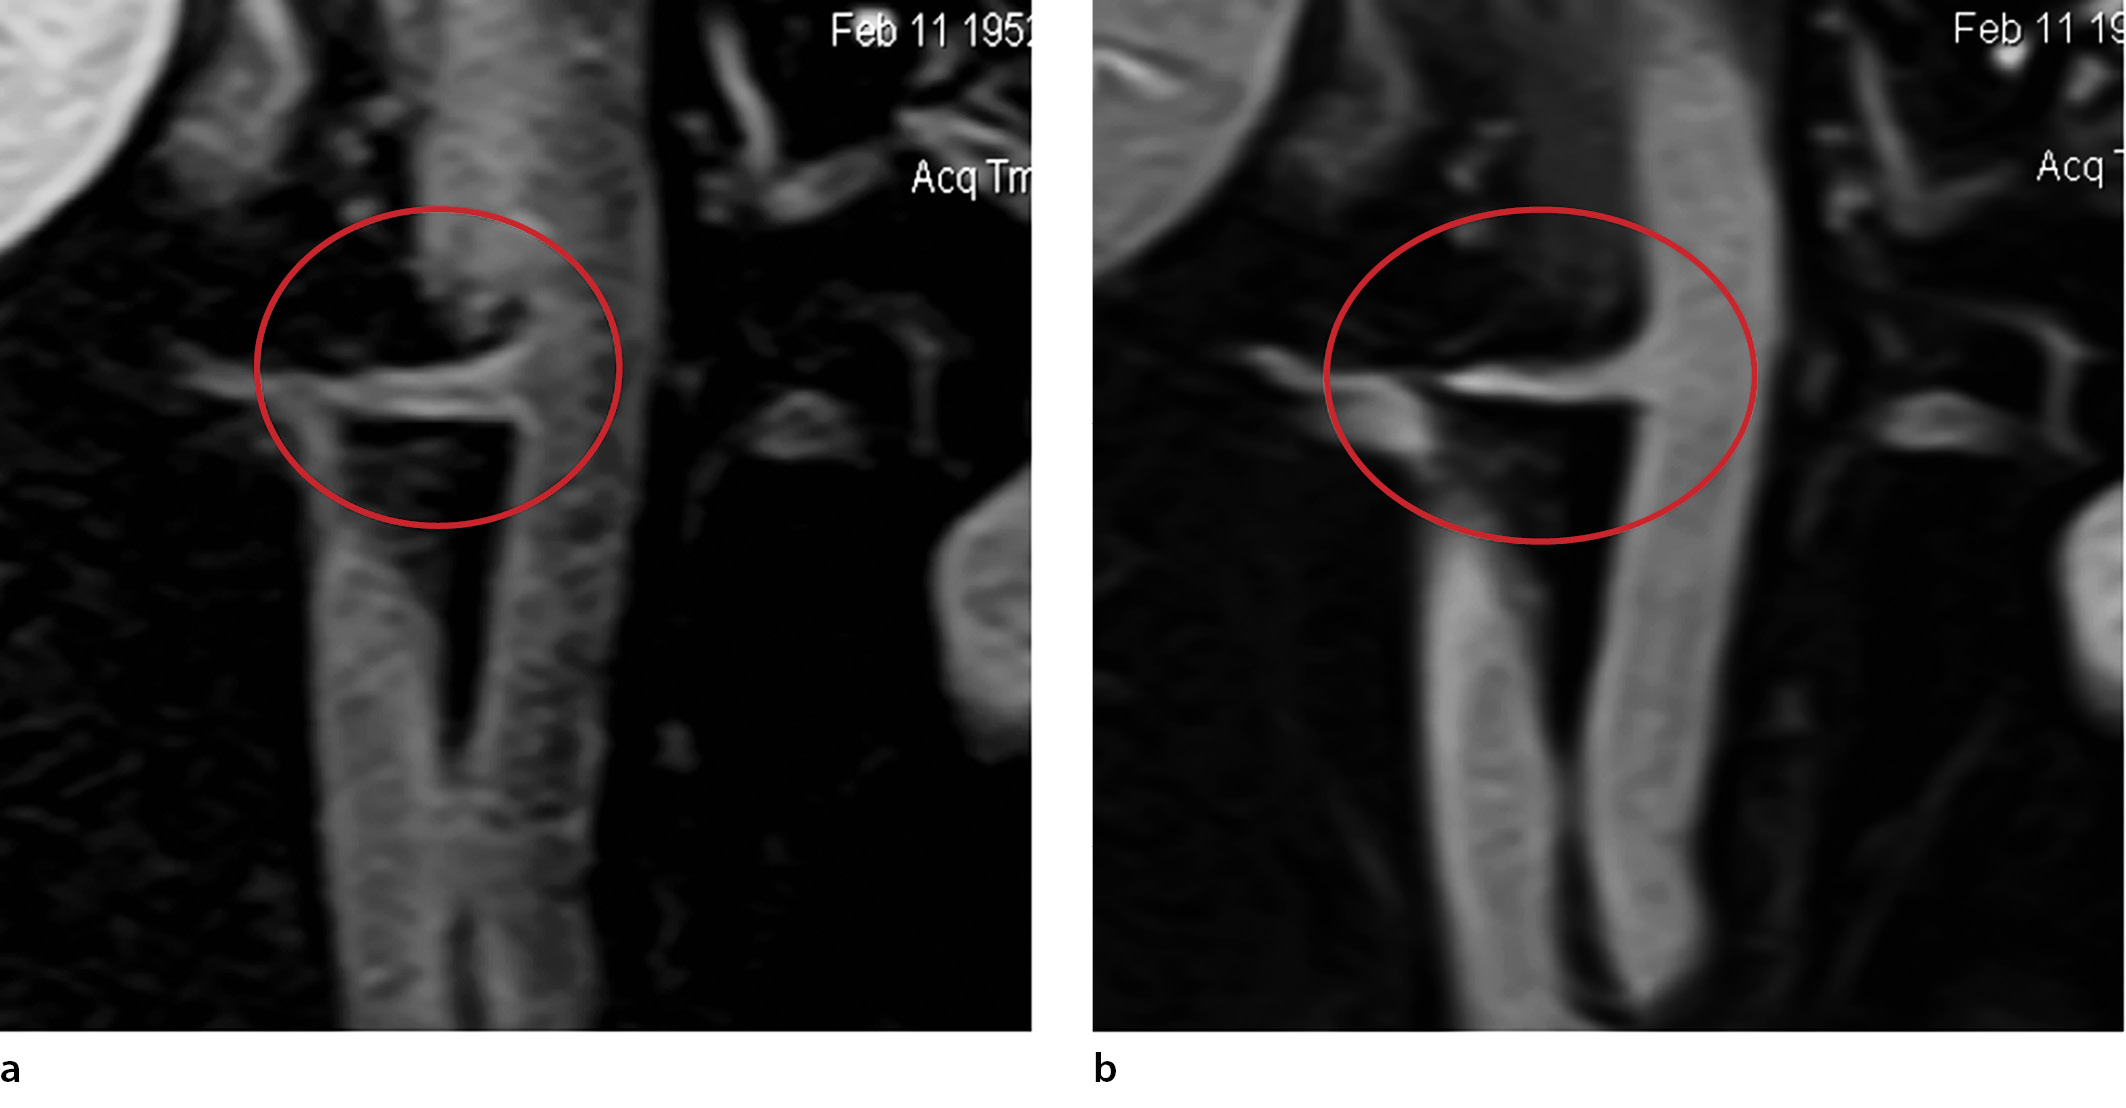

Методы регистрации исходов

Анализ накопления контраста в стенке почечных артерий осуществлялся следующим образом. На рабочей станции с помощью программного обеспечения определялась интенсивность МРТ-сигнала от стенки артерий на Т1-взвешенных спин-эхо-изображениях до и после введения контраста. МРТ-картина усиления МР-сигнала от стенок почечных артерий представлена на рис. 1. Затем рассчитывался индекс усиления (ИУ) МРТ-сигнала как отношение постконтрастного Т1-изображения к исходному:

ИУ = (Интенсивность Т1-взв SE)контраст /(Интенсивность Т1-взв SE)исходно.

Рис. 1. Магнитно-резонансная томография брюшной аорты и отходящих от нее почечных артерий в коронарной проекции на Т1- взвешенном спин-эхо-изображении до (а) и после (б) контрастирования. Выделена область интереса – ствол правой почечной артерии с четко видимыми стенками [30].

Показатель ИУ измерялся в трех точках – устье, средняя часть ствола и дистальная часть с частичным переходом на сегментарные ветви.